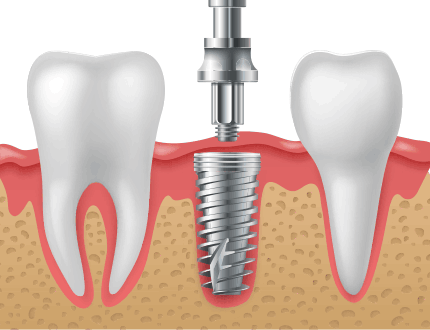

연조직, 치조골의 손상을 줄여주는 최소침습 임플란트

연조직과 치조골의 손상을 최소화하고 기타 인공물들의 사용을 최소화하여 환자의 손상에 따른 불편감을 줄여주는 최소침습 개념의 임플란트 시스템입니다. 치조골의 폭이 좁거나 상태가 좋지 않은 경우에도 골이식 혹은 골성형을 최소화하여 식립할 수 있는 최소침습 임플란트입니다.

절개하지 않는 임플란트

최소침습(무절개)방식의 임플란트